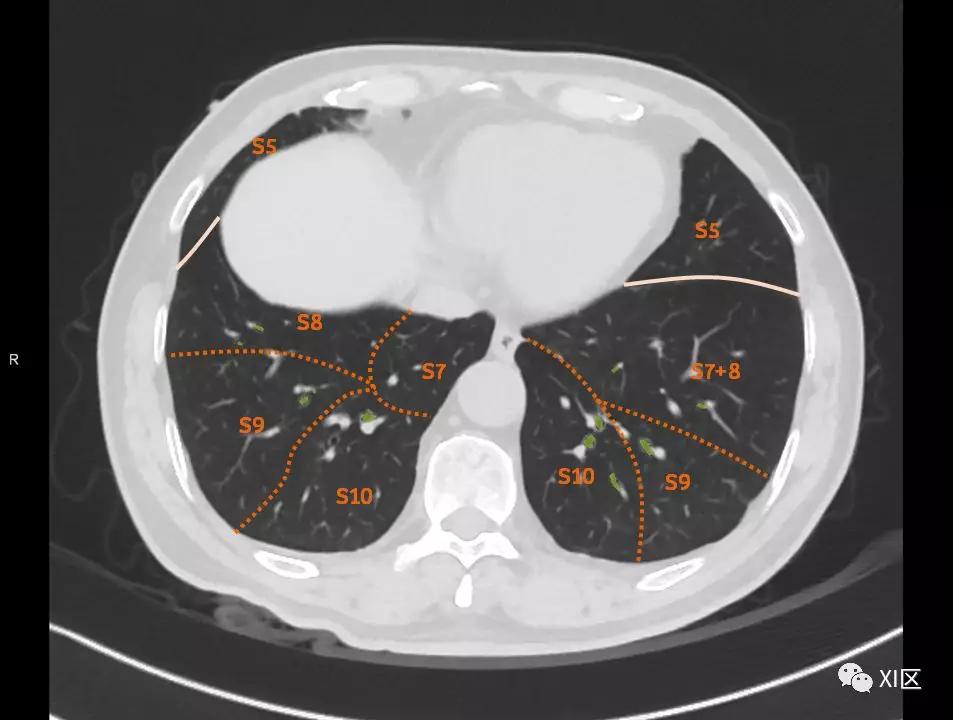

肺的断层分段示意图

在进行肺的分段时,可以上下观察浏览,沿着相应气管的走形可以更容易准确地进行分段。